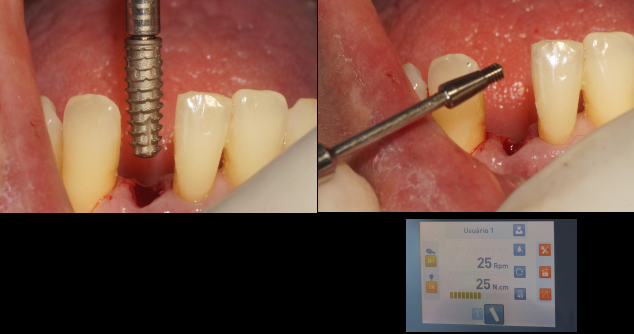

O fragmento coronário e a raiz residual foram removidos e após a curetagem do alvéolo iniciou-se a fresagem do mesmo, seguindo o protocolo de instalação do implante Maestro para o mesmo ser ativado de forma precoce (35 dias após a instalação). Utilizamos a fresa lança helicoidal e na sequência foi utilizada a fresa cônica de 3.5, ambas as fresas com rotação de 600 RPM. Após a fresagem, o implante Maestro de 3.5 X 11.0 mm foi inserido no alvéolo, atingindo um torque de instalação de 25 Ncm, seguindo assim o protocolo de instalação do implante Maestro para carga precoce. Na sequência, foi realizada a sutura e a prótese adesiva foi instalada.